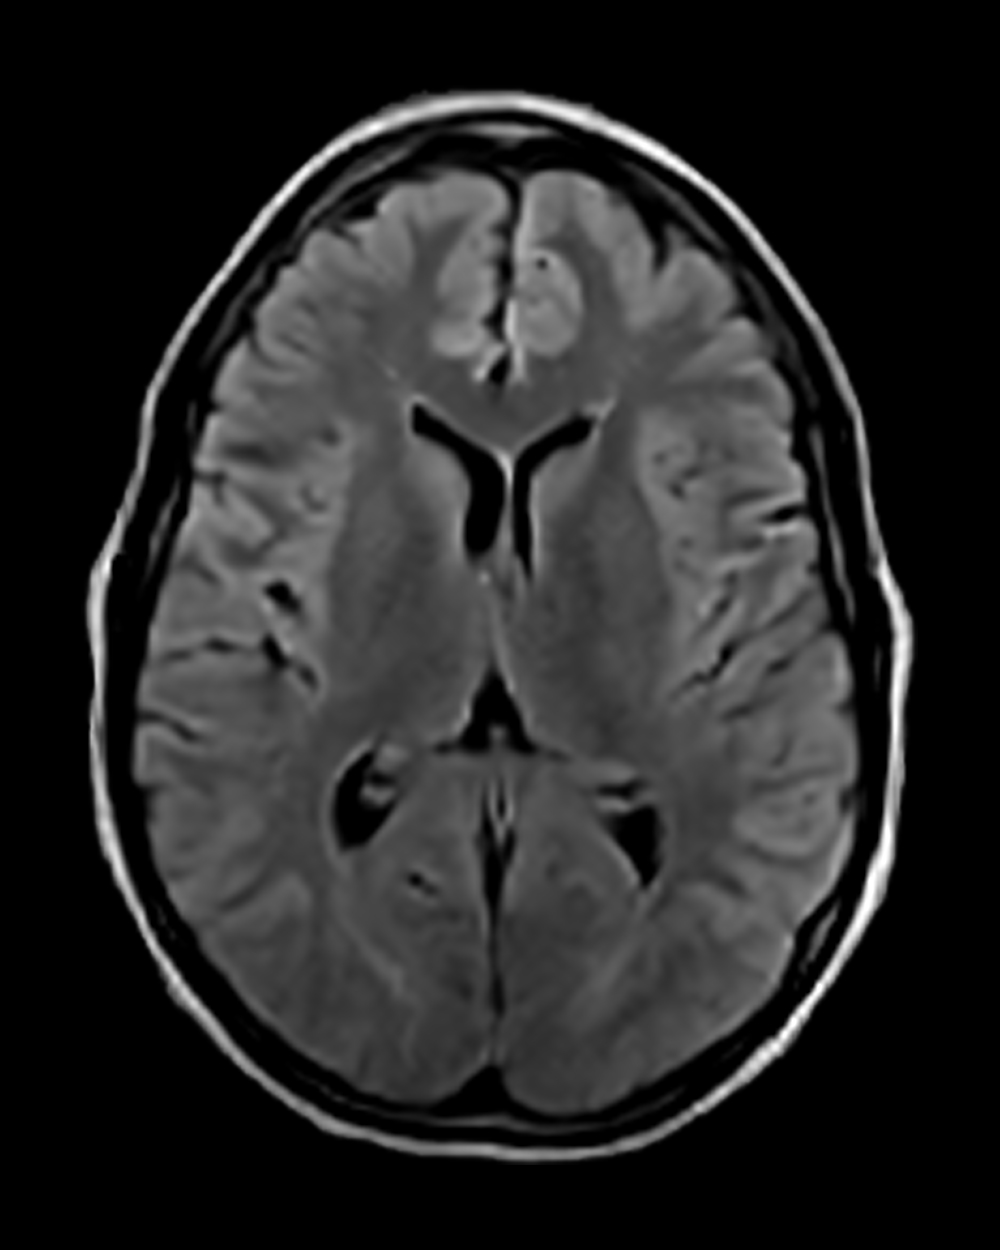

A tissue clock for identifying treatable strokes

For wake-up strokes or unknown onset, DWI-FLAIR mismatch can serve as a tissue-based marker to help determine stroke age—critical for guiding treatment decisions.